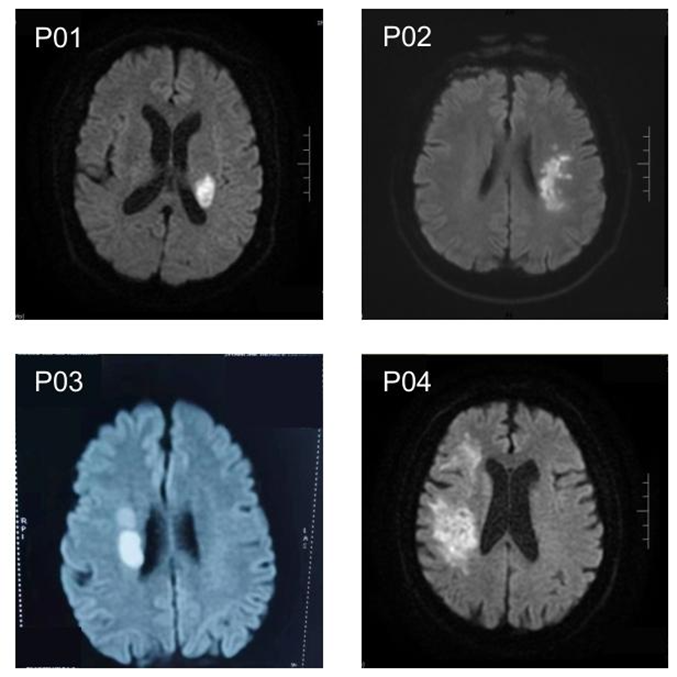

图1  四名患者的磁共振成像(MRI)图像。图中亮度增强的不对称区域与脑部多发性缺血性梗死病灶相符。

受试者与病灶特征(图 1):实验招募 4 名单侧上肢运动障碍患者(均为缺血性脑卒中,Fugl-Meyer 评分 24-43 分,评分越低功能障碍越严重),其脑部 MRI 图像(图 1)显示,亮度增强的不对称区域集中于基底节区、侧脑室旁等运动功能关键脑区,与患者上肢运动障碍症状直接相关,为实验任务设计与神经信号解码提供了临床病理依据。所有患者均处于非急性或亚急性期,具备基本配合能力,符合伦理审批要求(青岛海慈医院伦理批号:2024HC01LS16)。